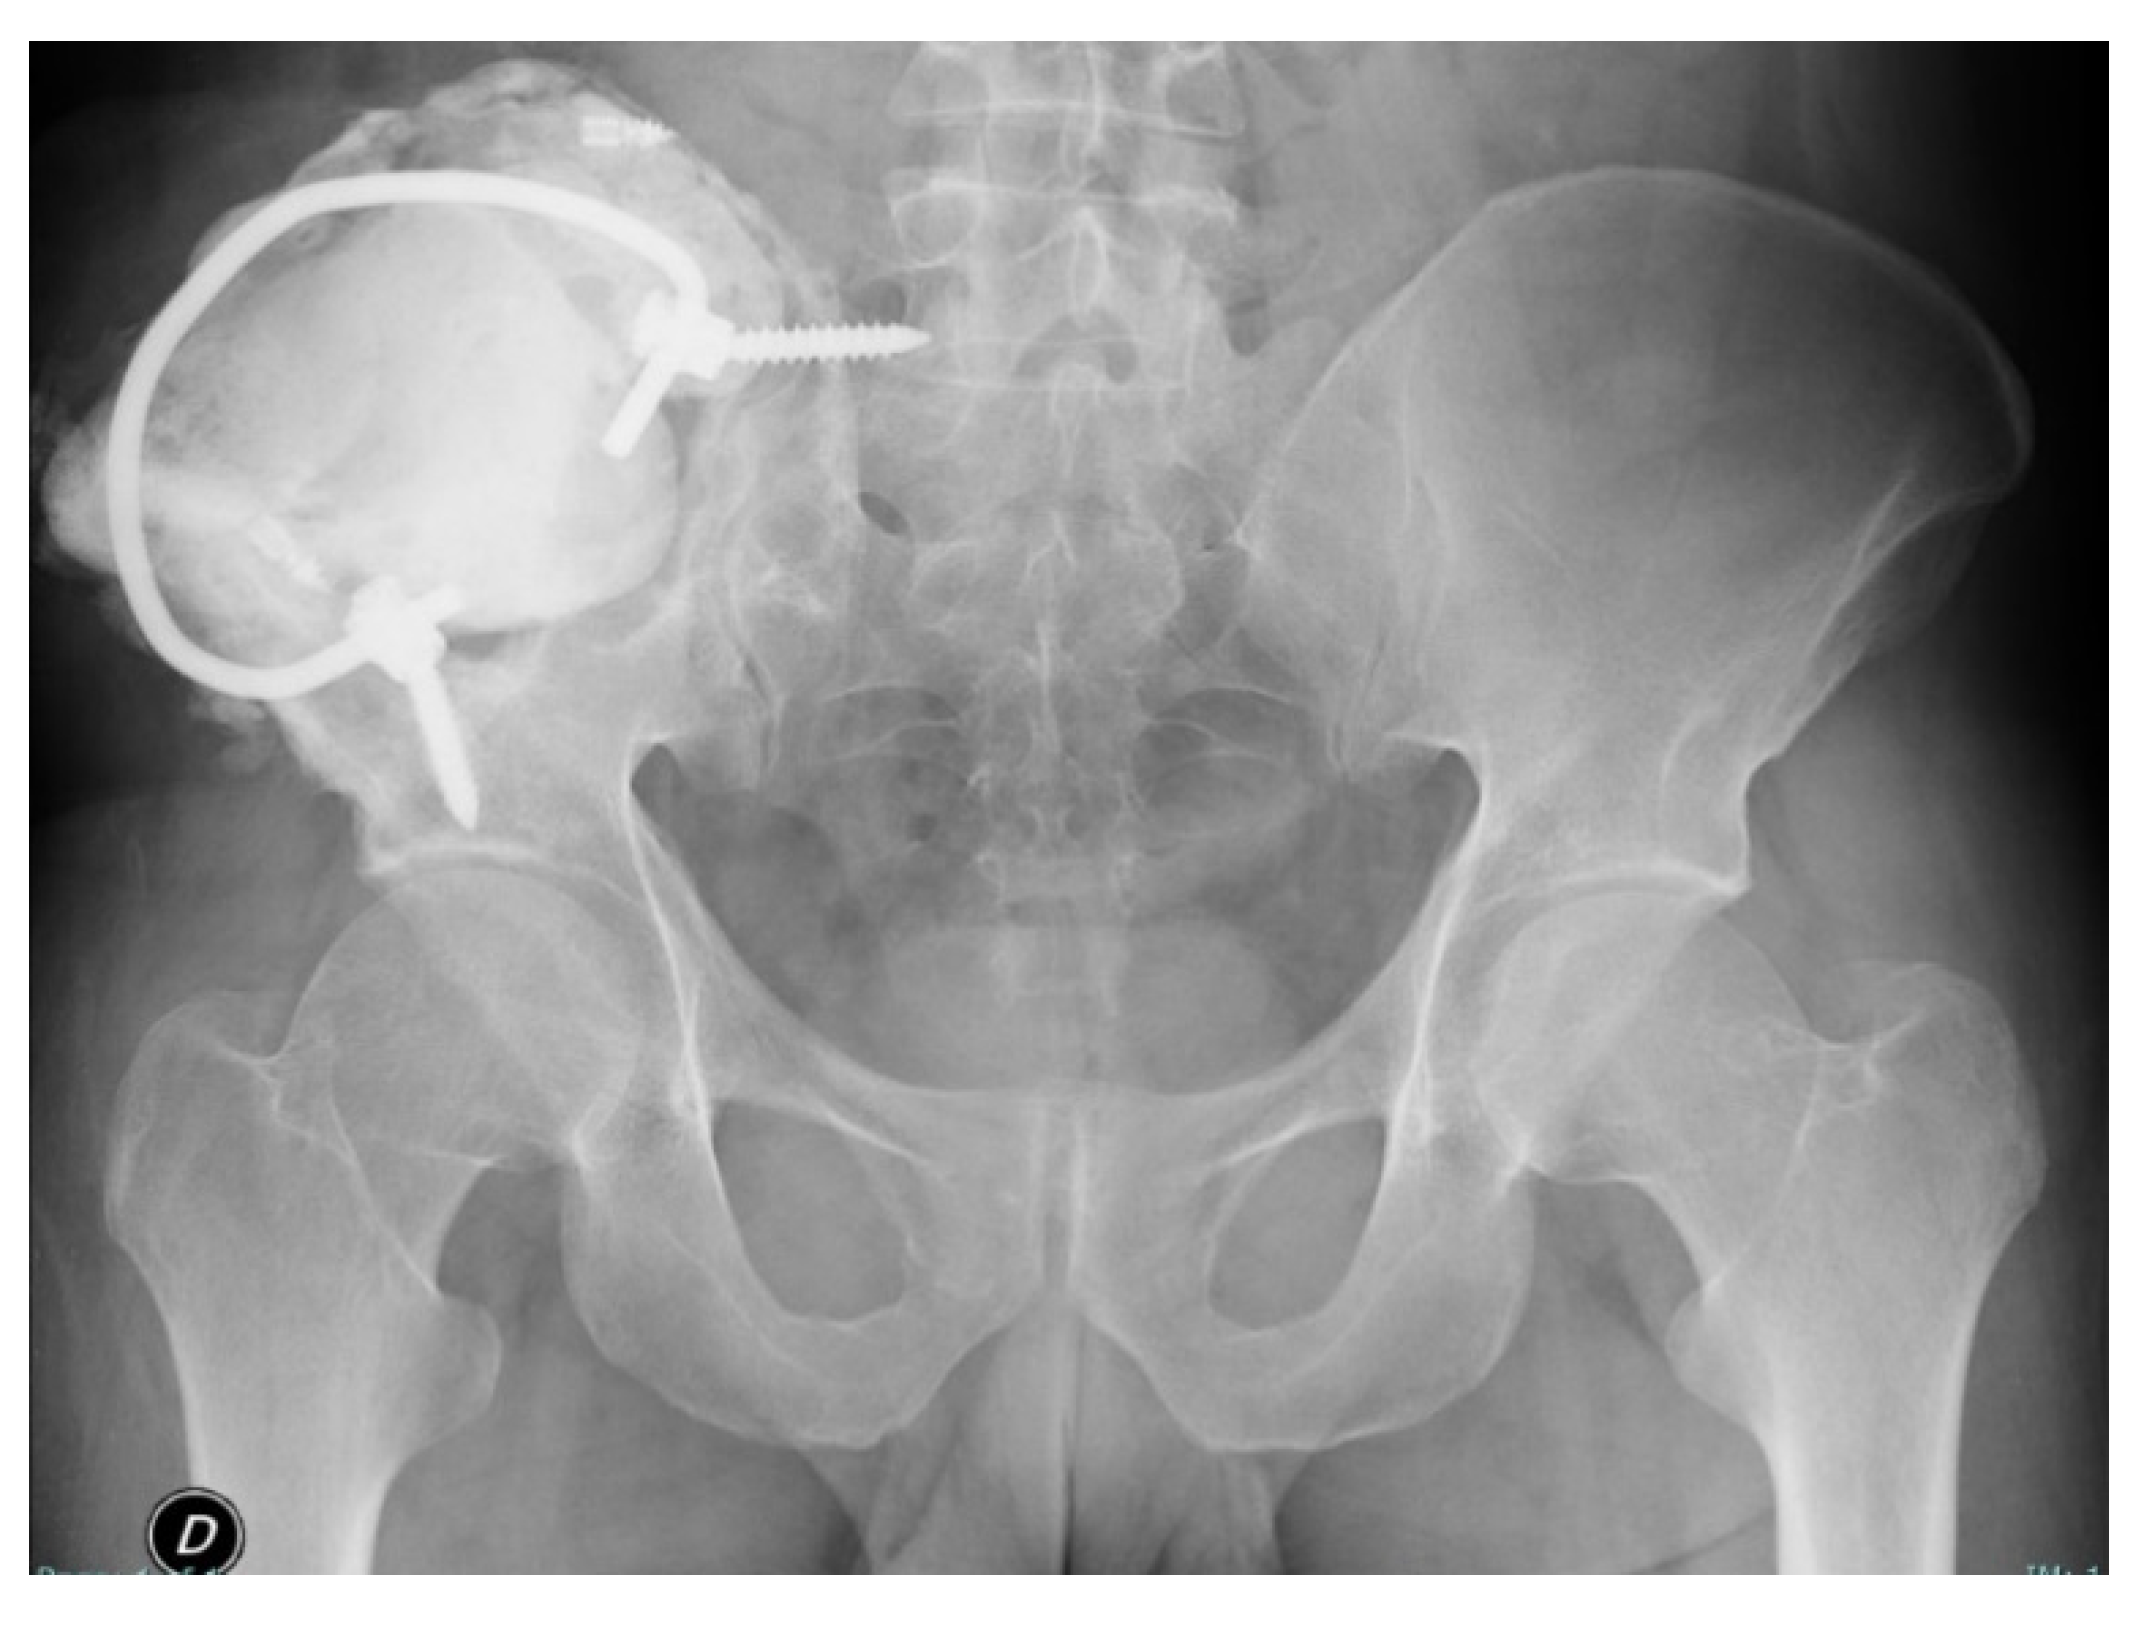

2.2. Surgery

2.3. Postoperative Period